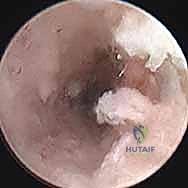

ولكن اليوم، وبفضل التطور المذهل في التقنيات الجراحية والتصوير الطبي، نشهد ثورة حقيقية في علاج هذه الحالة المعقدة. تقنية التدخل المحدود (Percutaneous Surgery)، المدعومة بالتنظير المفصلي عالي الدقة، غيرت قواعد اللعبة تماماً. هذه التقنية تتيح للجراح الماهر الوصول إلى العظم المكسور، تنظيف منطقة عدم الالتئام، وضع الطعوم العظمية، وتثبيت العظم بمسامير ضغط دقيقة، كل ذلك عبر ثقوب صغيرة جداً في الجلد.

ما يميز الأستاذ الدكتور محمد هطيف هو سعيه الدائم لجلب أحدث ما توصل إليه الطب العالمي إلى اليمن. هو من رواد استخدام تقنية التدخل المحدود بالمنظار في جراحات الرسغ. عيادته وغرف العمليات التي يشرف عليها مجهزة بأحدث تقنيات التنظير المفصلي بتقنية 4K (Arthroscopy 4K)، والتي تمنح رؤية مكبرة وفائقة الوضوح لأدق تفاصيل المفصل، مما يسمح بإجراء التدخلات الجراحية بأقصى درجات الأمان والدقة. كما يُعد خبيراً في الجراحات الميكروسكوبية (Microsurgery) الضرورية للتعامل مع الأوعية الدموية والأعصاب الدقيقة في اليد.

هذه هي التقنية المتقدمة التي يبرع فيها الأستاذ الدكتور محمد هطيف في صنعاء. بدلاً من فتح الرسغ، يتم إجراء العملية بأكملها من خلال شقوق دقيقة لا تتجاوز 2-3 مليمترات، تحت إرشاد جهاز الأشعة المرئية (Fluoroscopy) وبمساعدة المنظار المفصلي الدقيق.